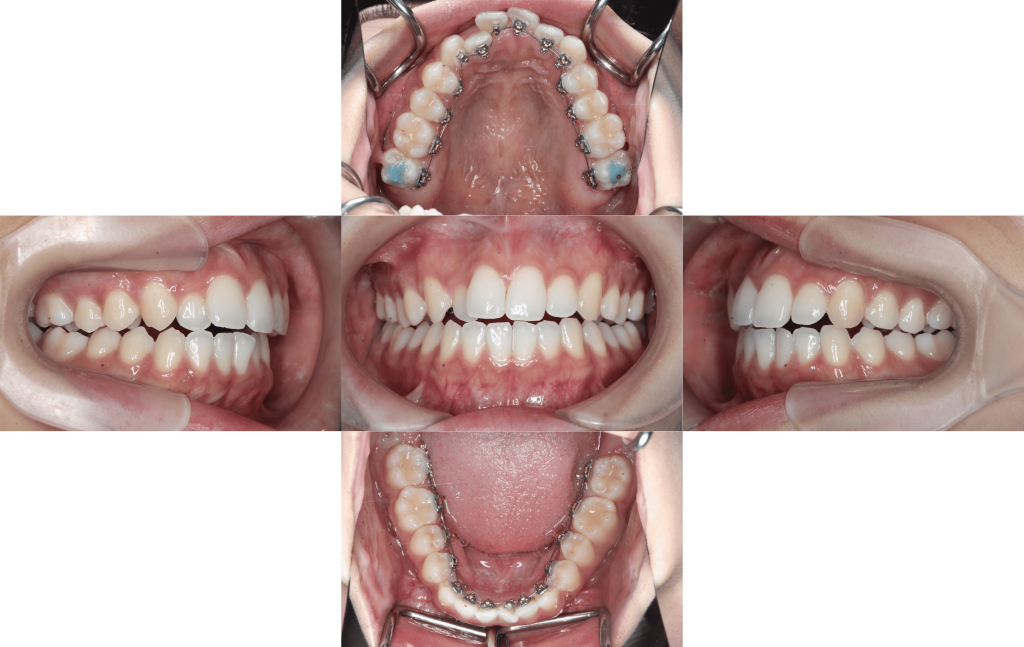

約1年経過